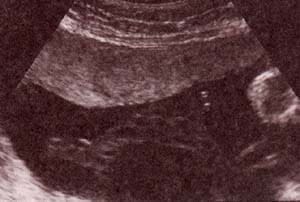

Diagnóstico Prenatal -  genitales externos xx Diagnóstico Prenatal -  genitales externos xx

fig. 49.– (a). genitales externos xx. labios mayores (1) . 32 semanas. fig. 49. – (b). labios menores fusionados (2). 32 semanas.